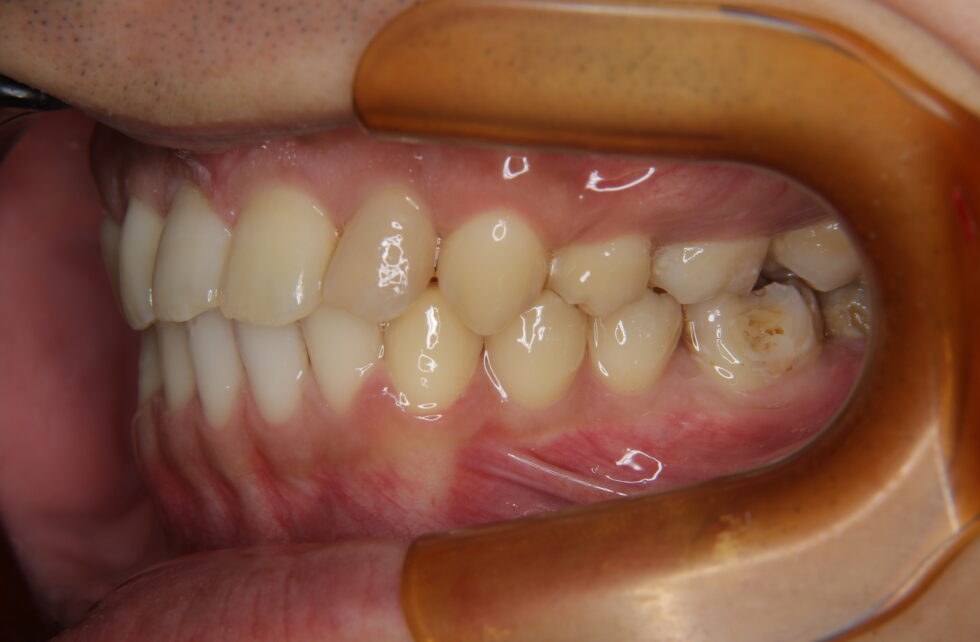

大臼歯関係はⅡ級で上顎前突となっていたが、特筆すべきは、左側の小臼歯、大臼歯すべてが内側に倒れ、すれ違ってかみ合っておらず、上下顎小臼歯、大臼歯が著しく挺出して、咬合平面も著しく歪んでいた。右側臼歯部のすれ違い咬合を伴う骨格性上顎前突と診断して、矯正用アンカースクリューとアンカープレートを併用し上顎舌側、下顎唇側マルチブラケット措置を使用して動的治療を行った。治療は右側臼歯部をまずかみ合わせるところから開始した。その後、上顎左右側小臼歯を抜歯していただき。上顎前歯の後退を行った。治療前は食事をするたびに臼歯が歯肉を噛んでしまい出血したり、ひどい肩こりがあったとのことであったが、動的治療後はこれらの症状が消失し良好な状態になったとのことであった。

動的治療期間3年11カ月間